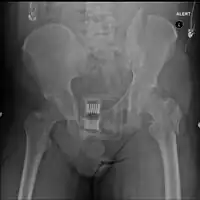

Pelvic vertical shear fracture

Fractures of the superior (in two places) and inferior pubic rami on the person's right, in a person who has had prior hip replacements